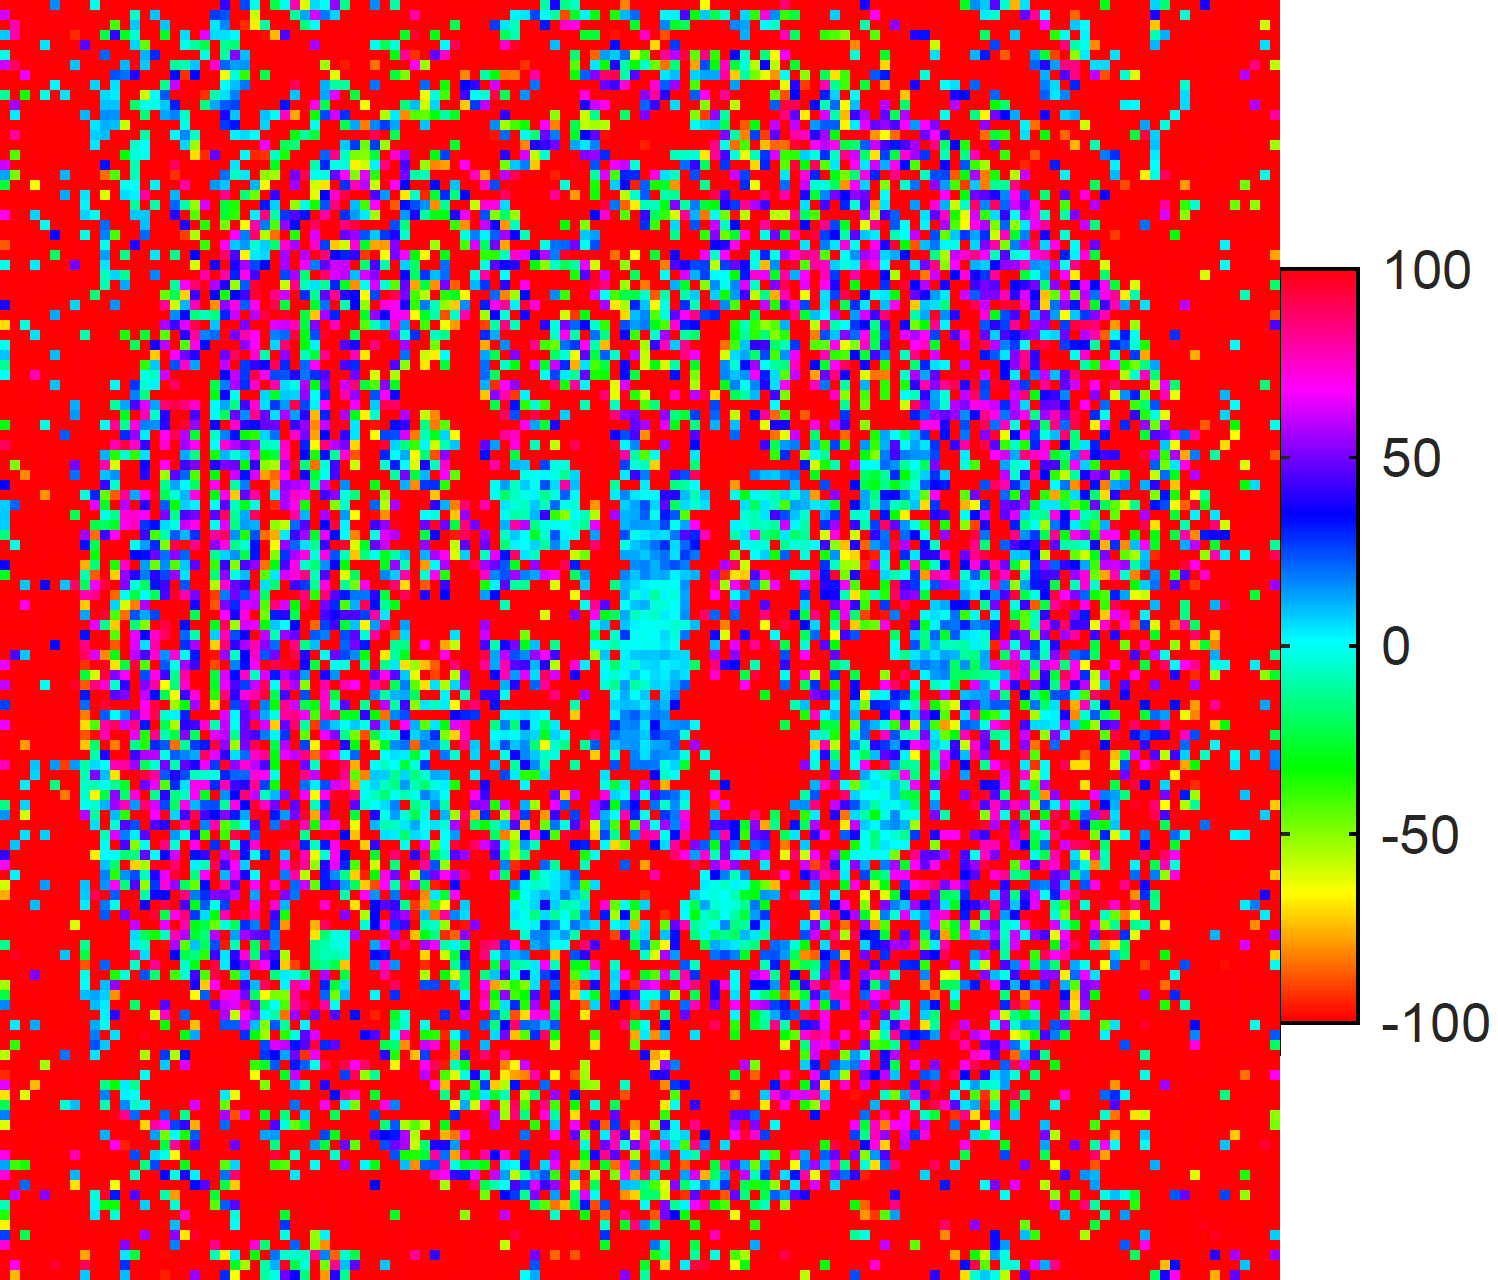

4.3 Verification of TEUSQA with prospective acquisition

Figure 8 shows the difference in estimated T1subscript𝑇1T_{1} and T2subscript𝑇2T_{2} maps for the test and retest acquisition. We select the spheres where the nominal T1subscript𝑇1T_{1} and T2subscript𝑇2T_{2} values are expected to be mapped correctly by the sequence settings. In these spheres the mean difference between maps from test and retest is close to zero. Outside of these spheres large differences can be observed. The bias in the T1subscript𝑇1T_{1} and T2subscript𝑇2T_{2} estimates compared to the nominal values was on average about 5%percent55\% and 28%percent2828\% respectively in the selected spheres. A detailed comparison with the nominal values is presented in the figures 6 and 7. Following this we computed ηpACQsubscriptsuperscript𝜂𝐴𝐶𝑄𝑝\eta^{ACQ}_{p} over the selected spheres which was found to be 0.2210.2210.221 with 95%percent9595\% confidence bounds [0.201,0.241]0.2010.241[0.201,0.241] for T1subscript𝑇1T_{1} and 0.1220.1220.122 with [0.111,0.134]0.1110.134[0.111,0.134] 95%percent9595\% confidence bounds for T2subscript𝑇2T_{2}. The predicted ηpsubscript𝜂𝑝\eta_{p} for T1subscript𝑇1T_{1} and T2subscript𝑇2T_{2} were 0.2540.2540.254 and 0.1250.1250.125, respectively. The predicted ηpsubscript𝜂𝑝\eta_{p} for T1subscript𝑇1T_{1} was within 12%percent1212\% of the observed ηpACQsubscriptsuperscript𝜂𝐴𝐶𝑄𝑝\eta^{ACQ}_{p} while for T2subscript𝑇2T_{2} it was within the 95%percent9595\% confidence bounds of observed ηpACQsubscriptsuperscript𝜂𝐴𝐶𝑄𝑝\eta^{ACQ}_{p}.

Refer to caption

(a) T1subscript𝑇1T_{1} difference map from T1subscript𝑇1T_{1} array

(b) T2subscript𝑇2T_{2} difference map from T1subscript𝑇1T_{1} array

(c) T1subscript𝑇1T_{1} difference map from T2subscript𝑇2T_{2} array

(d) T2subscript𝑇2T_{2} difference map from T2subscript𝑇2T_{2} array

Fig. 8: Test-retest difference maps for T1subscript𝑇1T_{1} (left) and T2subscript𝑇2T_{2} (right) estimates in the T1subscript𝑇1T_{1} (top) and T2subscript𝑇2T_{2} array (bottom) of the ISMRM model 130 phantom [22] (units in ms). Scans were made using prospective undersampling using the Halton pattern with acceleration factor R=32𝑅32R=32.